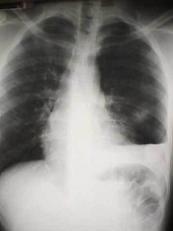

Hemotorace stang masiv Hemotorace stang masiv

Hemotorace

drept masiv Hemotorace stang

Imagine CT Radiografie efectuata in ortostatism